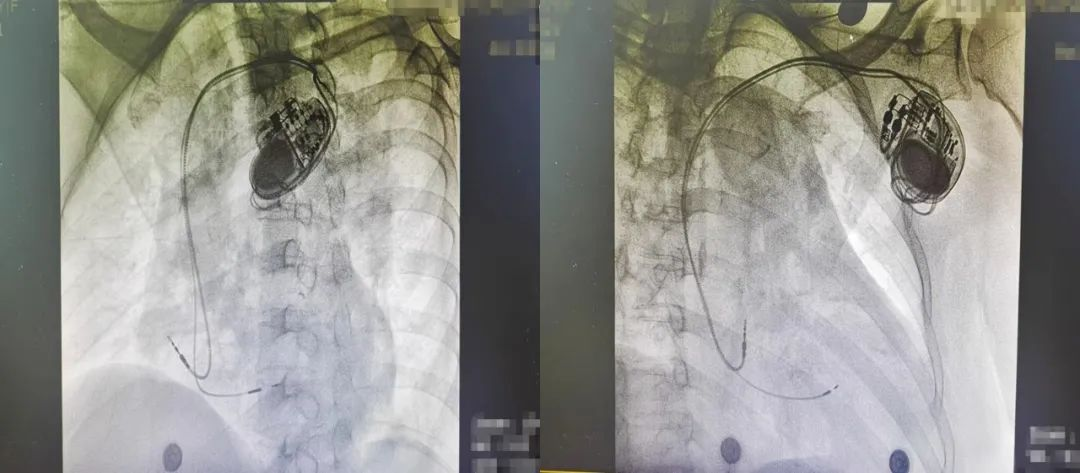

▲术后影像

▲术前及术后QRS波宽

虽然左束支起搏疗效好,但手术难度较大,其要求医生在术中反复寻找、精确定位,将电极从右室间隔侧旋入至左侧间隔侧,并能精确定位到左束支上。经过充分的术前准备,电生理团队在X线和多导电生理仪的指引下准确找到患者左束支起搏区域,最终成功将电极植入左束支区域,完美实现了左束支起搏,术前测量QRS波宽为135ms,术后达峰时间为56ms,QRS波宽度86ms,起搏器工作正常,患者恢复良好。